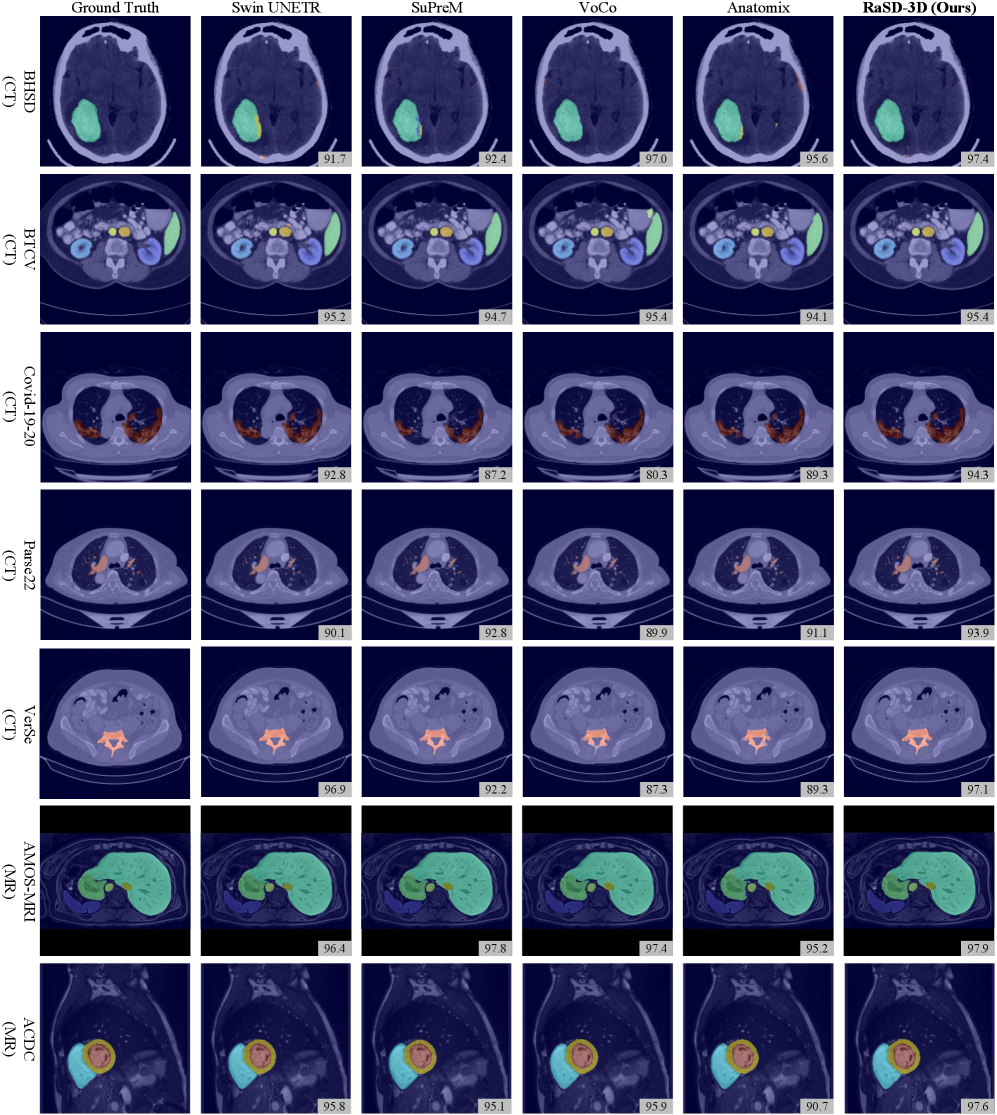

Our RaSD-3D exhibits strong performance across a wide spectrum of CT and MR downstream tasks, demonstrating that synthetic data pre-training can effectively optimize CT and MR representations. We benchmarked our RaSD-3D on 14 CT datasets and 6 MR datasets spanning nearly all human organs, covering 17 segmentation and 3 classification tasks. Comparisons were made against three state-of-the-art (SOTA) self-supervised pre-training models (Swin UNETR (pretrained) [tang2022self], SuPreM [li2024well], VoCo [wu2024voco, wu2024large]), a from-scratch baseline (Swin transformer (scratch) [hatamizadeh2021swin]), and a most-related randomized synthesis-based FM (Anatomix [dey2025learning]). For segmentation, their backbones were integrated into Swin UNETR, while for classification, the backbones were paired with a classification head following [wu2024large]. Dice score and AUC were used for the evaluation of segmentation and classification tasks.

2.2.1 CT image segmentation

On CT datasets (Fig. 2 a-l), our RaSD demonstrates strong generalization capabilities across anatomical regions. Compared with random initialization (“scratch”), our RaSD yields consistent and substantial improvements on all 12 CT segmentation tasks. Especially, on the TotalSegmentator (a), IRCADb (d), and VerSe20 (l), it brings over 6% improvement, showing the effectiveness of our learning on synthetic images. Against real-data pre-training methods, RaSD achieves the best or tied-best performance on IRCADb (d), Covid-19-20 (h), and WHS-CT (k). Consistent performance is observed across diverse CT segmentation tasks, including BHSD (b), CHAOS (e), MSD09 (f), Parse22 (i), and SegThor (j), with RaSD performing within 1% of the best method.

Compared with Anatomix, our RaSD outperformed it in all 12 CT segmentation tasks, demonstrating the effectiveness of learning through randomized synthesis and disentanglement. While Anatomix also employs randomized data for FM training, its design primarily benefits modalities with unstable intensity distributions, which constrains its performance on intensity-stable modalities. Consequently, Anatomix shows markedly limited performance on the TotalSegmentator and BHSD datasets, in some cases performing worse than models with random initialization. In contrast, RaSD consistently achieves high performance across all datasets, highlighting its robustness and generalizability across diverse CT modalities.

2.2.2 MR image segmentation

On MR datasets (Fig. 2 o–s), our RaSD continues to yield strong gains without requiring real-data pre-training. It attains the highest performance on 3 out of 5 tasks (o, q, s), outperforming all real-data pre-trained FMs. Moreover, it consistently outperforms at least one comparative method on the remaining two tasks (p, q). These results collectively indicate that the representations acquired through synthetic data pre-training not only transfer effectively to MR modalities but also exhibit particular advantages in segmenting diverse anatomical structures, including brain tumors, whole-body organs, and cardiac anatomy.

Compared with Anatomix, our RaSD also achieved superior performance in MR segmentation. Although Anatomix demonstrates comparable results in brain, liver, and heart segmentation tasks (o, q, r, s), its performance on abdominal multi-organ segmentation (AMOS-MR, p) is severely limited, in some cases falling below that of models with random initialization. This limitation arises from Anatomix’s suppression of appearance differences, which restricts the representation of organ and structural features and reduces feature discriminability. In contrast, RaSD consistently delivers stable performance gains, even outperforming Swin UNTER, which is pre-trained on real images.

2.2.3 CT/MR classification

Beyond segmentation, RaSD also demonstrates compelling cross-task generalization in classification datasets (Fig. 2 m, n, t).

On CT-based datasets, RaSD achieves an AUC of 98.8% on CC-CCII (m), matching VoCo and surpassing SuPreM and Swin-UNETR by up to 0.5%. On LUNA16 (n), RaSD attains 98.1%, outperforming all other methods except VoCo, with only a small gap of 0.6% compared to the best method. For the MR image benchmark (t), RaSD reaches 80.9% in AUC, surpassing from scratch baseline by 1.2% and closing the performance gap with top-performing methods within 2%. These results confirm that RaSD not only overcomes the appearance constraints of Anatomix but also establishes a more robust and generalizable synthesis-based pre-training paradigm through randomized disentanglement.